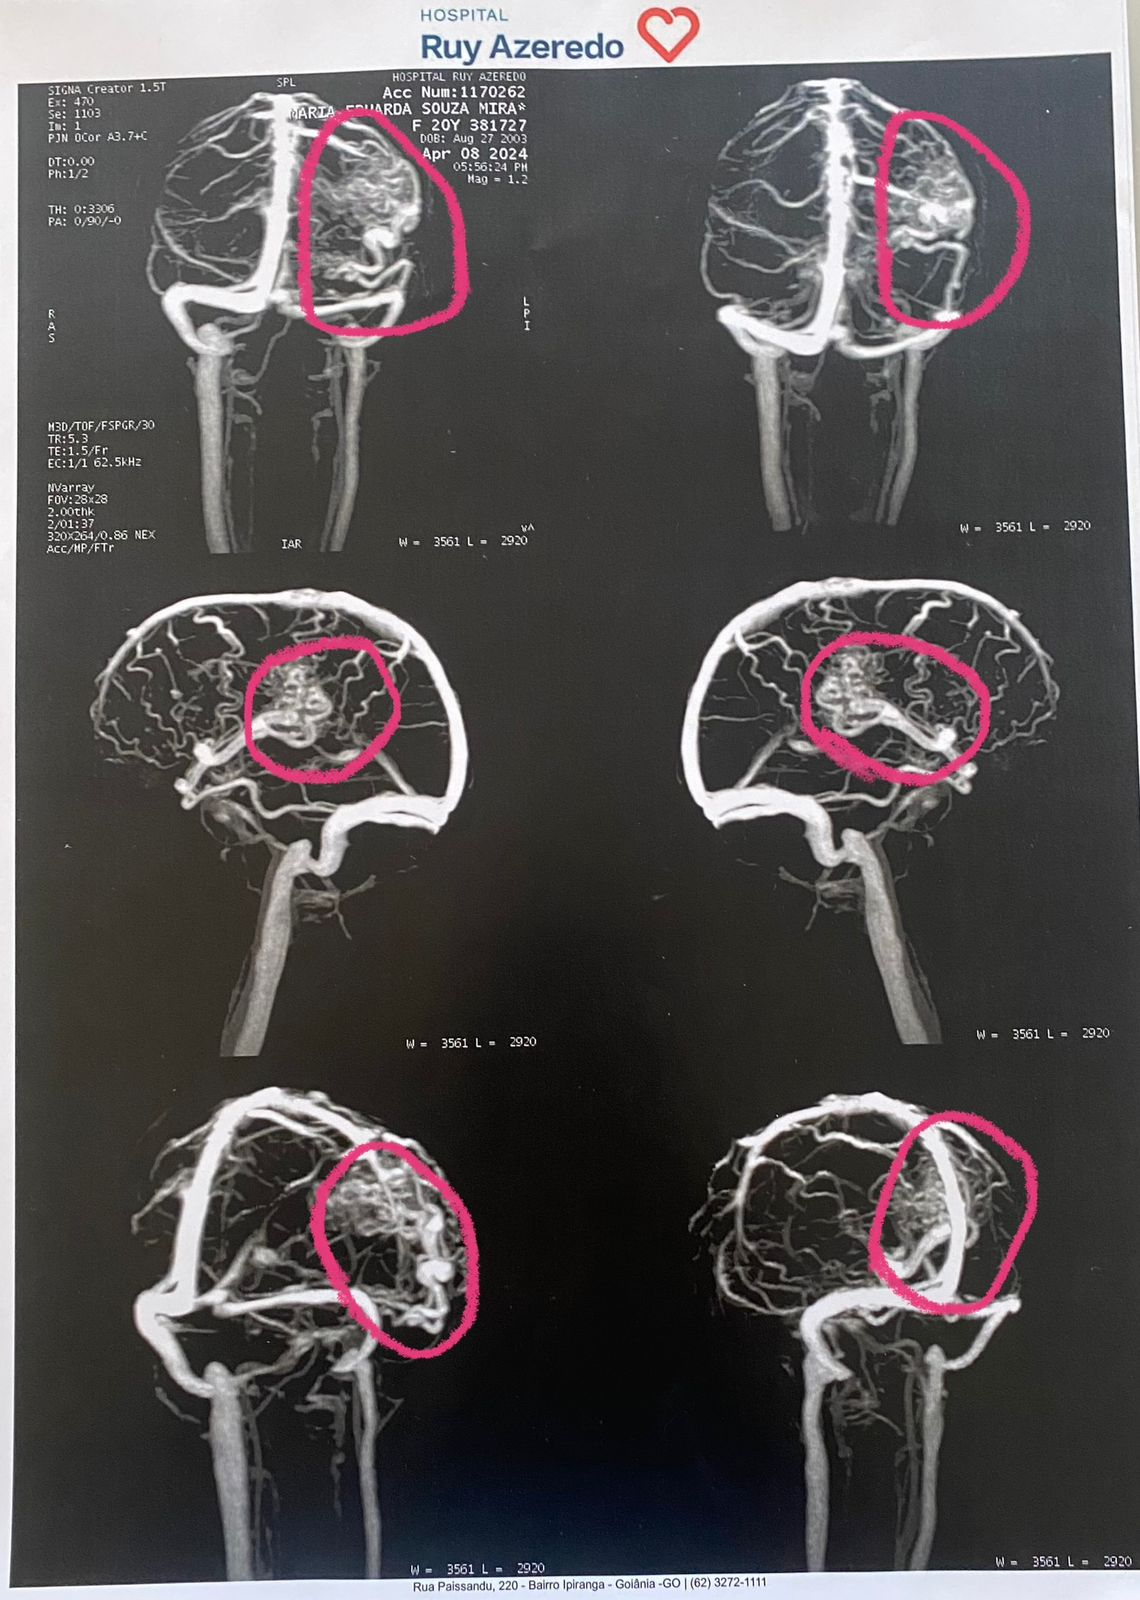

Infelizmente, HOJE, não venho pra nada divertido aqui. Há duas semanas descobri que eu nasci com uma doença, rara, grave e silenciosa, tão silenciosa que só aos 20 anos os sintomas começaram a aparecer, só agora recebi o diagnóstico da Malformação Arteriovenosa Intracraniana (MAV).

Resumidamente é uma doença caracterizada pela presença de um enovelado de vasos anormais que se interpõem entre artérias e veias, semelhante a um novelo de lã, que em função dos diferentes níveis de pressão das artérias e veias, o nidus pode romper, provocando hemorragia, no meu caso está localizada próximo a parte do cérebro responsável pelos movimentos, na hipótese de uma hemorragia pode ocasionar em uma paralisia de um lado do corpo ou até mesmo a perca da fala. A cirurgia que é o tratamento mais comum pra cura dessa doença, é por volta de 200 mil reais, e nenhum convênio cobre ela.resumidamente é uma doença caracterizada pela presença de um enovelado de vasos anormais que se interpõem entre artérias e veias, semelhante a um novelo de lã, que em função dos diferentes níveis de pressão das artérias e veias, o nidus pode romper, provocando hemorragia, no meu caso está localizada próximo a parte do cérebro responsável pelos movimentos, na hipótese de uma hemorragia pode ocasionar em uma paralisia de um lado do corpo ou até mesmo a perca da fala. A cirurgia que é o tratamento mais comum pra cura dessa doença, é por volta de 200 mil reais, e nenhum convênio cobre ela.